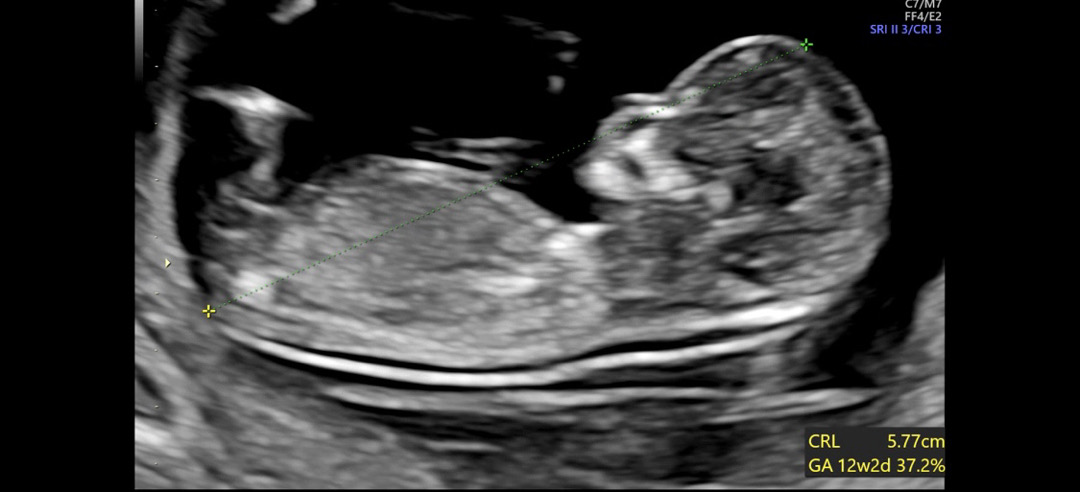

전 딸맘일까요 아들맘일까요 한번만 봐주세요

12주 2일 초음파에요 성별 넘 궁금해요ㅠㅜ